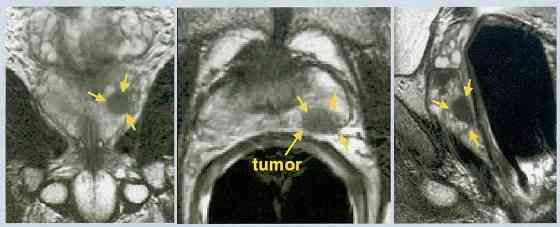

Obviously it's important to know where in the gland the cancer is found to ensure that the seeds include the posterior, peripheral zone as well as reach down to the apex (as the study below shows) also note that non-palpable lesions (T1c) may have more cancer in the anterior part or transitional zone (also review normal ultrasound anatomy, below) MRI may show the lesion and MRI spectroscopy may be even more sensitive